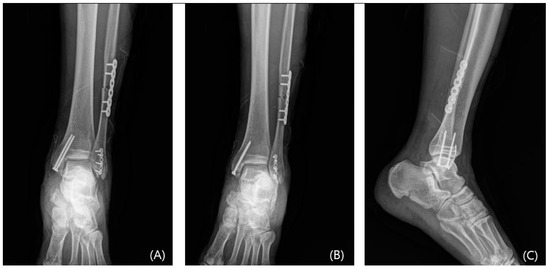

In cases of instability, a mini-plate (Arix Hand System, Jeil Medical, Seoul, Republic of Korea) is shaped to cover the Wagstaffe fracture and secured using 2.0 mm cortical screws and locking screws (Figure 3). For smaller fractures, screws were applied to the proximal and distal sections of the mini-plate at the fracture site. Screw fixation was performed at the fracture site when possible (Figure 4). Subsequently, tibiofibular joint stability was assessed through arthroscopy. Figure 5 and Figure 6 show the preoperative plain X-ray and CT images of a 47-year-old female with a Wagstaffe fracture. Figure 7 shows the postoperative plain X-ray image of a Wagstaffe fracture treated with open reduction and internal fixation using the described technique. Postoperative CT images were used to further confirm the reduction and fixation (Figure 8).

Figure 7. The postoperative mortise, anteroposterior, and lateral radiographs (AC) showing mini-plate fixation for Wagstaffe tubercle fracture.